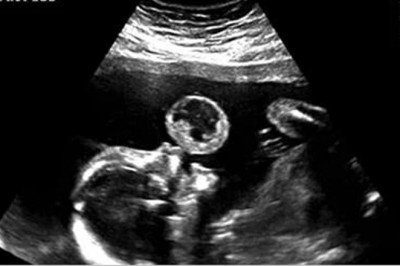

Mama myśli, że na USG widać jak jej maluch puszcza bańki. Wtedy lekarz przekazuję jej złe nowiny

Tammy Gonazalez z Miami na Florydzie robiła rutynowe badanie USG. Nagle zauważyła, że jej dziecko zdaje się wydmuchiwać z ust olbrzymią bańkę.